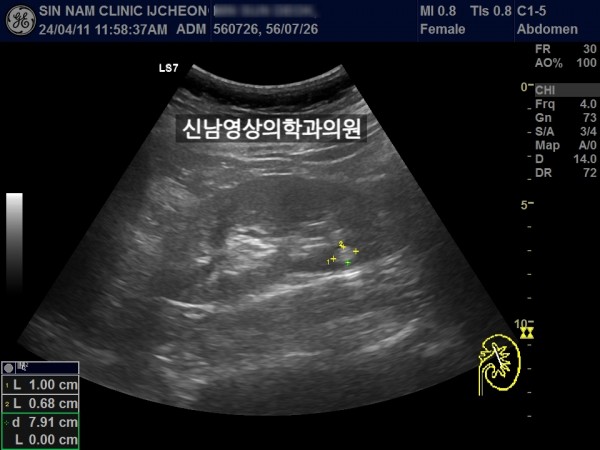

좌측 신장 지방혈관종 추적검사中 우측 신장의 종괴를 발견했습니다.

차후 신장암으로 수술하셨습니다.

초음파 당시 증세는 없었습니다.